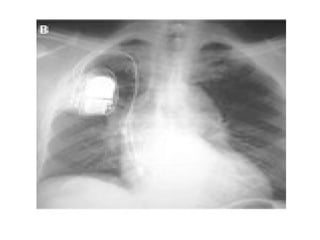

83 years old lady chronic AF , Dysphagia

An esophagogram obtained to evaluate dysphagia for solid food revealed a prominent impression of the left atrium on the esophagus , without evidence of obstruction.

CXR findings ?

Chest radiography (Panel A) revealed cardiomegaly (cardiothoracic ratio, 0.86), splaying of the carina, and an elevated left main bronchus (arrows). Plus PPM DDD

Echocardiogram showed massive biatrial enlargement (left larger than right),

An 83-year-old woman with long-standing atrial fibrillation who had previously undergone atrioventricular nodal ablation and pacemaker placement presented with symptoms of progressive heart failure. The patient was discharged home on medical management after prolonged diuresis.